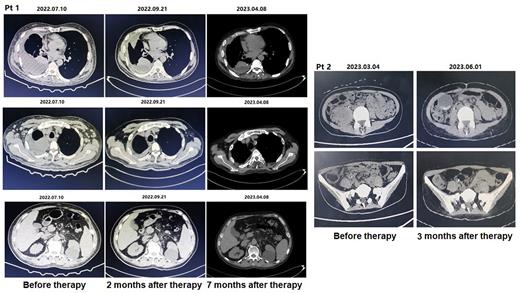

Seven patients with R/R B-NLH or even failure of anti-CD19 and CD22 chimeric antigen receptor (CAR) T cell therapy received InO combined with reduce dose R-GDP combination therapy. All patients received Rituximab (R) 375mg/m 2 intravenously (IV) on day -1, and InO 0.8 mg/m 2 (IV) on day 0. Then Gemcitabine (G) 500-1000mg/m 2(IV), Dexamethasone (D) 40 mg/day (IV) on day 1-4 and Cisplatin (P) 40-75mg/m 2 (IV) on day 1 of each 21-day cycle (±2 days). Treatment was continued for up to two cycles unless progressive disease (PD) or intolerable toxicity occurred. The primary endpoint of this study was the Complete remission (CR) and Overall response rate (ORR). The secondary endpoint of this study was Progression-free survival (PFS), Overall survival (OS) and Adverse events (AE), particularly hematological toxicity. In our study, the response evaluation was detected using computed tomography (CT) or PET-CT.

Seven patients with R/R B-NLH received 1-2 cycles of InO combined with reduce dose R-GDP therapy. Three patients did not respond to anti-CD19 and CD22 CAR-T cell therapy or their disease progressed again. The other four patients did not respond to more than 3 lines of combined immunochemotherapy and never achieved Partial response (PR) or CR. Four patients with R/R B-NLH who received 1-2cycles of InO combined with reduce dose R-GDP therapy achieved CR and survived to this day. Three of the four patients had previously received anti-CD19 and CD22 CAR-T cell therapy. Two patients with R/R B-NLH achieved PR after one cycle of InO combined with reduce dose R-GDP therapy, the other one patient achieved Stable disease (SD) only. One R/R B-NLH patient who achieved CR after one cycle of this salvage therapy had a PFS of one year to date without any other treatments. The other three R/R B-NLH patients who achieved CR after 1-2 cycles of this salvage therapy had a PFS of 3-6 months without any other treatments. The other two patients who achieved PR after 1 cycle of this salvage therapy survived 7 months and 2 months, while the only one patient who achieved SD survived one month without any other treatment. The main AE of this study was hematological toxicity. Three patients were defined as 3-4 grade of neutropenia, four patients were defined as 3-4 grade of anemia and three patients were defined as 3-4 grade of thrombocytopenia in this study. Except for one patient who was defined as grade 3 of thrombocytopenia recovered nine months after this salvage therapy, all other patients recovered two to three months after this study. There have been no deaths from severe infections due to hematological toxicity.